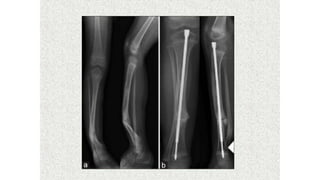

This document discusses a disease and its investigation and management. It begins by introducing Dr. Aniket Wankhede from MGIMS Sevagram and asks what the disease is. It then asks how the disease happens and discusses its causes. Next it asks how the disease appears on x-rays and describes symptoms some people experience living with it. Finally, it asks how the disease will be investigated and managed.